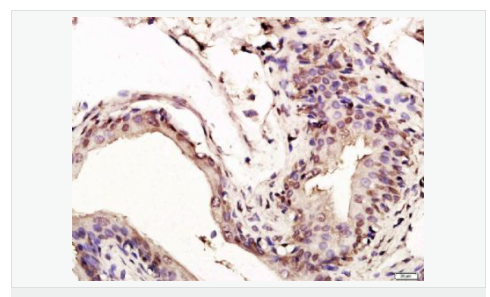

| 產(chǎn)品應(yīng)用 | WB=1:1000-2000 ELISA=1:1000-5000 IHC-P=1:100-500 IHC-F=1:100-500 Flow-Cyt=1ug/Test ICC=1:100-500 IF=1:100-500 (石蠟切片需做抗原修復(fù)) not yet tested in other applications. optimal dilutions/concentrations should be determined by the end user. |

| 細胞定位 | 細胞核 細胞漿 |